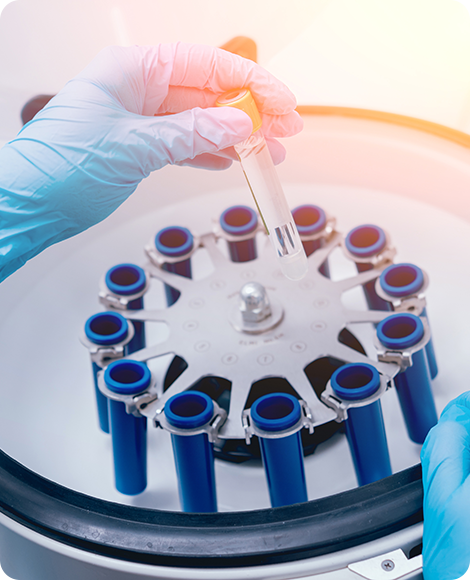

Our state-of-the-art laboratories, advanced testing methods, and expert staff make Alpha Labs Madurai a reliable choice for maintaining your health.